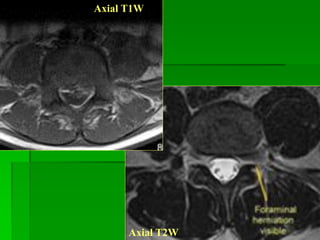

THOÁT VỊ ĐĨA ĐỆM (herniation): gồm

 Protrusion: Bờ của đĩa đệm nhô ra nhỏ hơn 50% của chu vi đĩa đệm

bình thường và phần thoát vị có chiều rộng > chiều cao. Gồm:

- Focal protrsion: Bờ của đĩa đệm nhô ra nhỏ hơn 25% của chu

vi đĩa đệm bình thường .

- Broad-based or diffuse protrusion: Bờ của đĩa đệm nhô ra 25-

50% của chu vi đĩa đệm bình thường.

- Far lateral diffuse protrusion: thoát vị bên xa vào vùng lỗ liên

hợp hay ngoài lỗ liên hợp.

 Extrusion (with or without free fragment): Bờ của đĩa đệm nhô ra

< 50% của chu vi đĩa đệm bình thường và phần thoát vị có chiều rộng

< chiều cao.

Thoát vị đĩa đệm tầng L5-S1, chèn rễ S1(T)

Thoát vị đĩa đệm

vào lỗ liên hợp